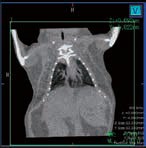

CosmoScan GX IIIは特に高い空間分解能を持ち、5µmまでの解像度と2.9µmのピクセルサイズ(FOV:8mm)を誇ります。これにより小さい骨の細かな解剖学的構造を含むex vivoサンプルの高品質な画像が得られます。

- 空間分解能 = 5µm 最小ピクセルサイズ = 2.9µm